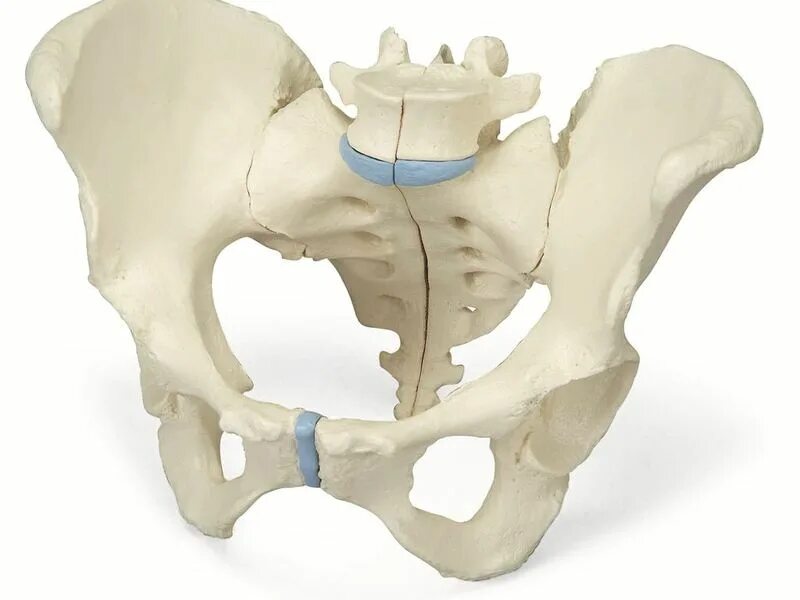

Кости таза анатомия крестец. тазовая поверхность крестца анатомия. крестец и копчик анатомия человека. крестцы таз человека.

Строение крестца. боковая масса крестца анатомия. крестец строение анатомия. где находится крестцовая кость.